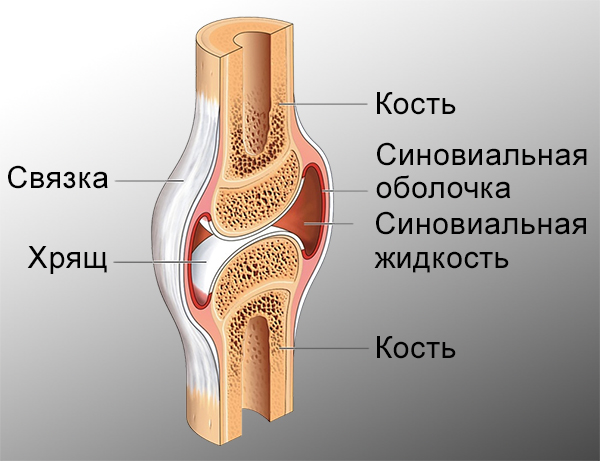

Суставная Жидкость и Головка Сустава: Обзор и Здоровье